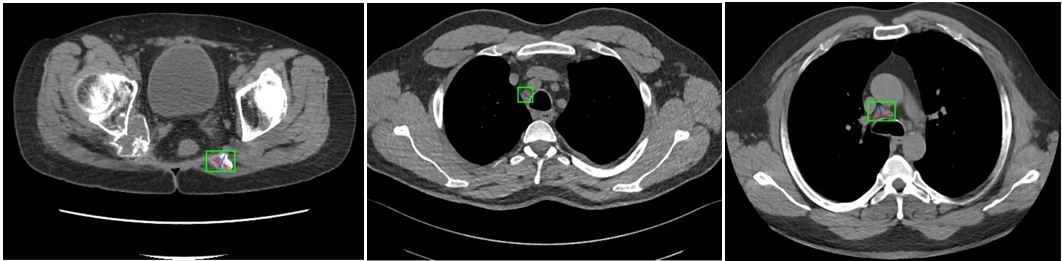

4.2.3 Small Object Detection in Medical Images

In the field of medical imaging, specialists are often tasked with early detection and identification of anomalies. Missing even barely visible or small abnormal cells can lead to serious repercussions for patients, including cancer and life-threatening conditions. These small-sized objects can be found as abnormalities in the retina of diabetic patients, early tumors, vascular plaques, etc. Despite the critical nature and potential life-threatening impact of this research area, only a handful of studies have tackled the challenges associated with detecting small objects in this crucial application. For those interested in this topic, the DeepLesion CT image dataset [111] has been selected as the benchmark due to the availability of the results for this particular dataset [126]. Sample images from this dataset are shown in Figure 15. This dataset is divided into three sets: training (70), validation (15), and test (15) sets [94]. Table V compares the accuracy and mAP of three transformer-based studies against both two-stage and one-stage detectors (results are compiled from their papers). The MS Transformer emerges as the best technique with this dataset, albeit with limited competition. Its primary innovation lies in self-supervised learning and the incorporation of a masking mechanism within a hierarchical transformer model. Overall, with an accuracy of 90.3 and an mAP of 89.6, this dataset appears to be less challenging compared to other medical imaging tasks, especially considering that some tumor detection tasks are virtually invisible to the human eyes.